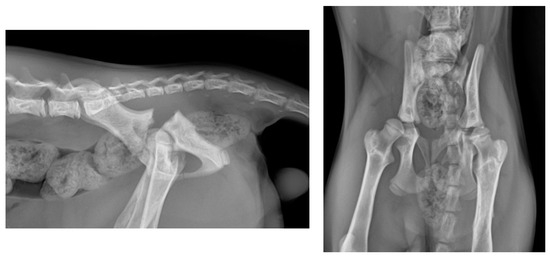

2.1. Preoperative Management

3. Results